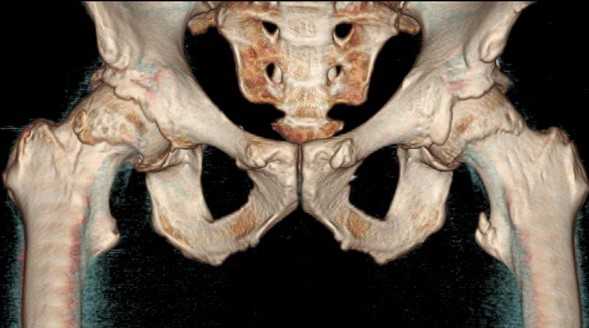

КТ тазобедренного сустава

Трехмерная реконструкция тазобедренных сочленений

КТ тазобедренного сустава используют для дифференциальной диагностики заболеваний, установления причины и характера патологического процесса.